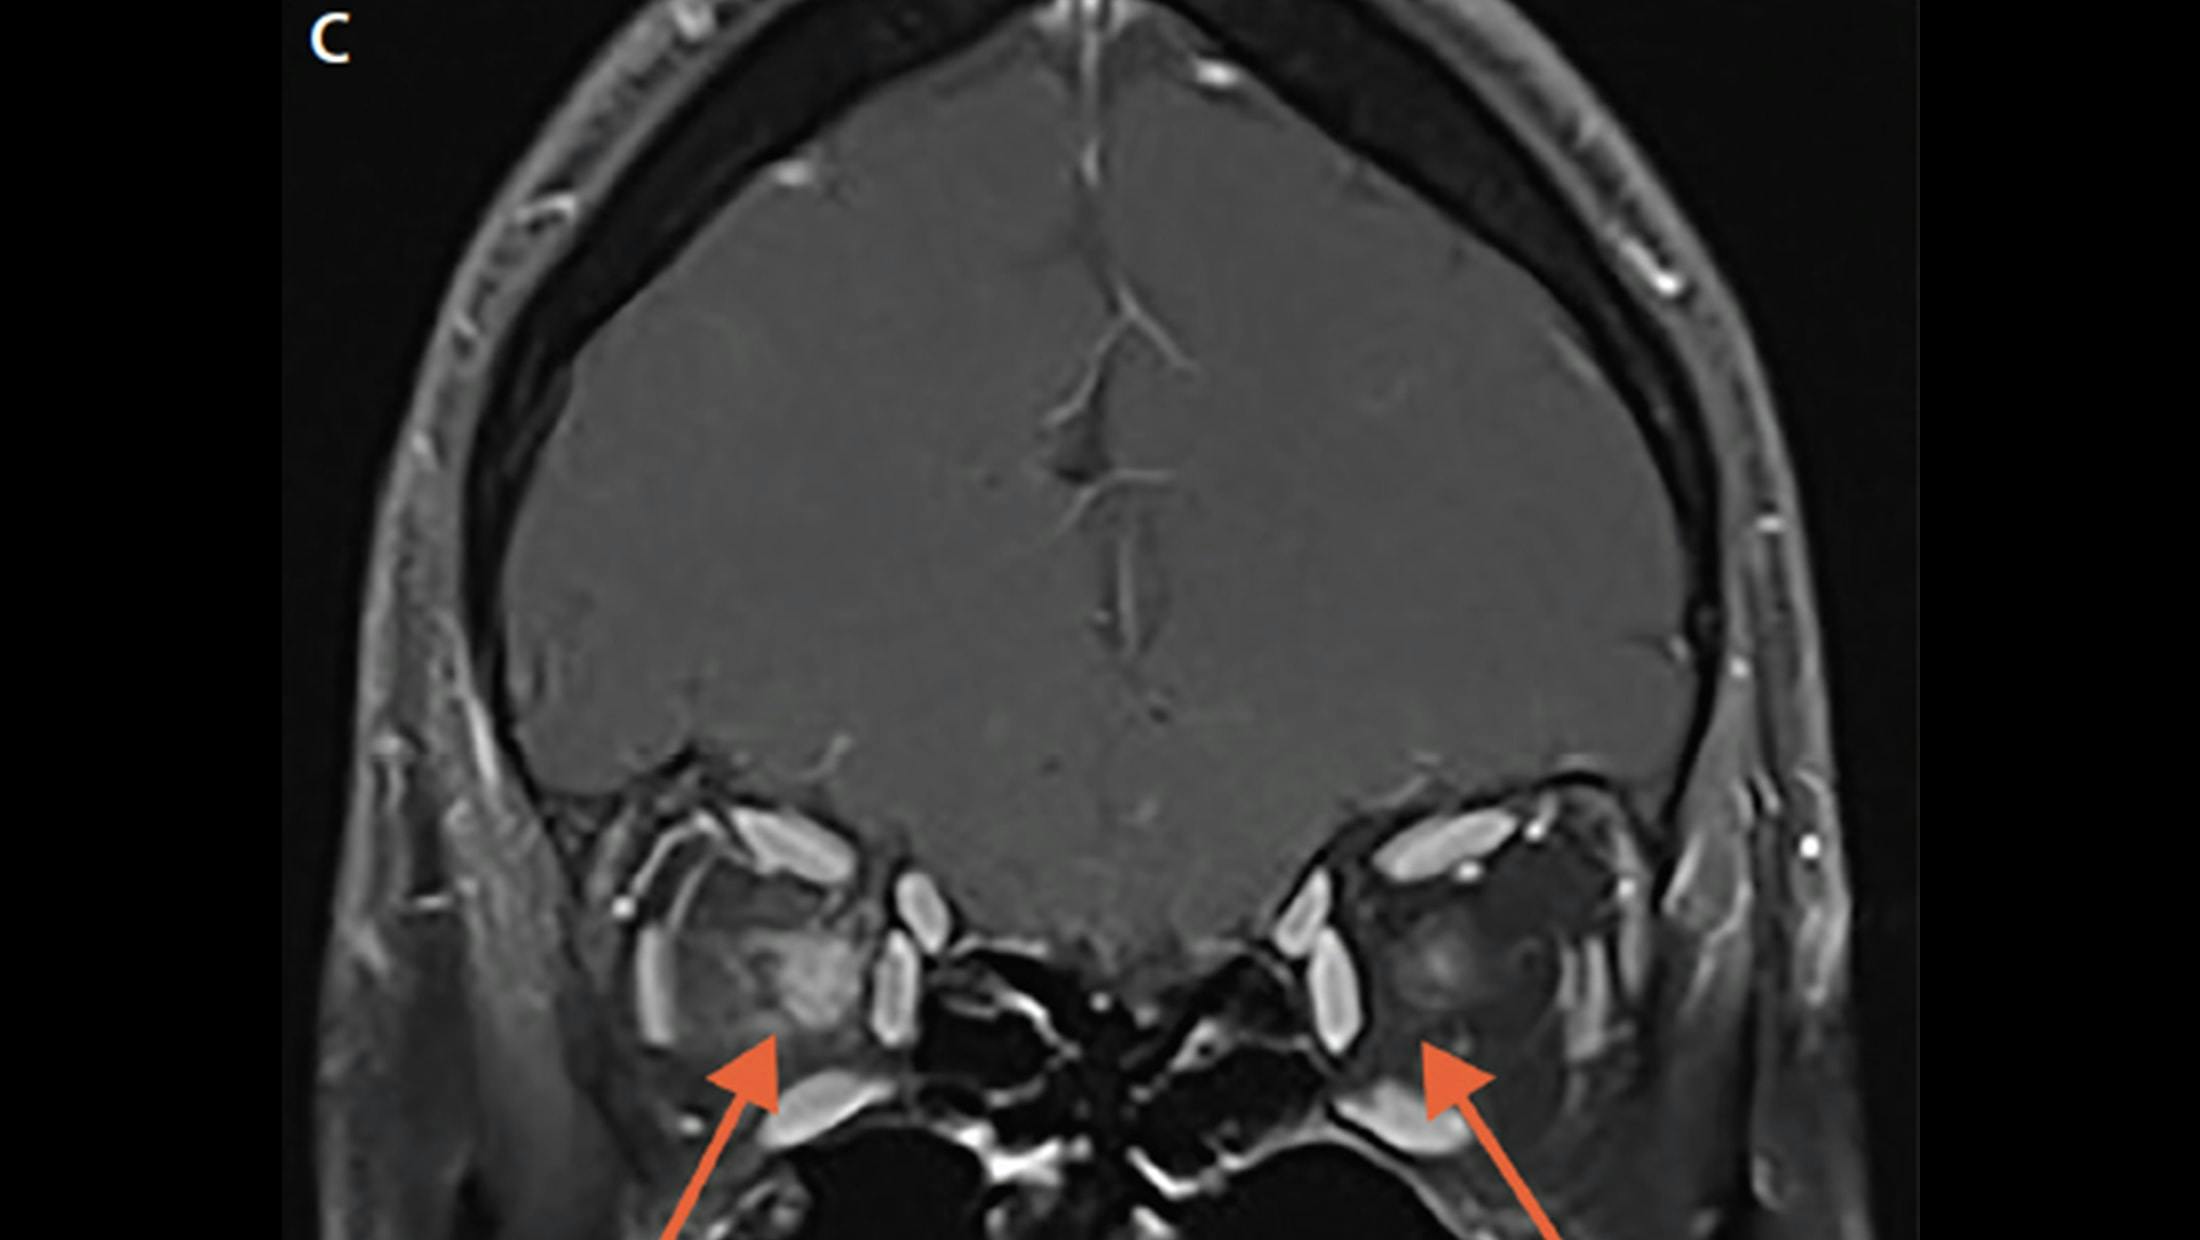

A. Axial T1 fat-saturated post-gadolinium MRI in a patient with AQP4+ NMOSD demonstrates bilateral optic neuritis over more than 50% of the optic nerves (arrows).